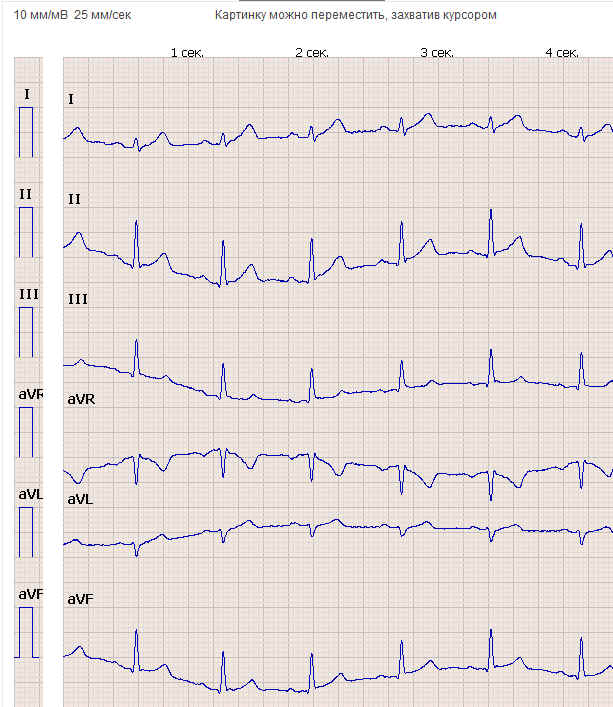

Пациенту, который нуждается в наблюдении врача, необходимо приобрести портативный электрокардиограф. Сегодня выбор домашних кардиографов очень обширен, потребителю доступны отечественные и зарубежные разработки. Основные характеристики, на которые нужно обратить внимание – это функциональные возможности прибора, безопасность эксплуатации, надёжность, простота использования и доступность для различных возрастных групп населения. Удобство подобных приборов заключается и в их малом размере и небольшом весе. При помощи этого портативного устройства пациент может самостоятельно зарегистрировать электрокардиограмму своего сердца. Сеанс записи ЭКГ состоит из стандартных этапов: подготовки и закрепления электродов на теле, присоединения к ним проводов и записи показателей сердечной деятельности согласно инструкции по эксплуатации конкретного аппарата, который используется пациентом. Специальный передатчик преобразует оперативно сделанную электрокардиограмму сердца в звуковые импульсы. Именно эти импульсы прибор передает по телефону в консультационный центр. Сам процесс передачи происходит следующим образом, нужно набрать номер медицинского учреждения с мобильного или стационарного телефона, затем просто приложить портативный электрокардиограф к трубке. Уже в медицинском центре полученный сигнал преобразуется в графическое изображение, которое и анализируется врачом-кардиологом. Интерпретация данных, отображаемых на мониторе, даёт возможность врачу оценить состояние сердечно-сосудистой системы пациента, поставить диагноз, дать необходимые рекомендации, а если это обоснованно немедленно направить к нему скорую помощь. Благодаря бурному развитию телемедицинских технологий, возможно перенаправить полученные результаты для дополнительного анализа в центральные кардиологические клиники. Для удобства реализации системы дистанционной кардиологической помощи рационально размещатьконсультационные центры по территориальному принципу: непосредственно при кардиоотделениях клинических больниц.